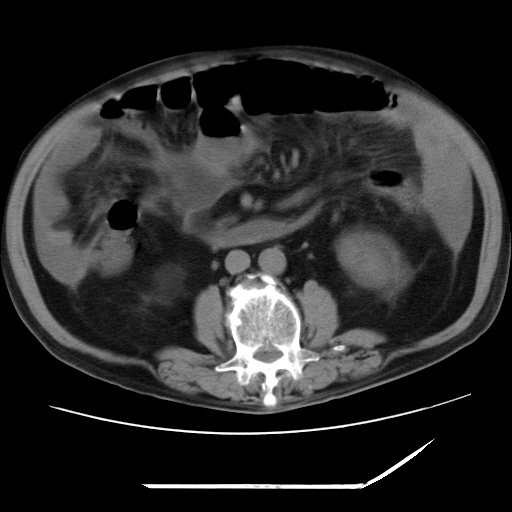

以下是引用zxl51642在2009-8-12 18:55:00的发言:[br]1、肠系膜脂肪浑浊,密度增高,腹水,支持腹膜炎诊断;2、右肾盂及输尿管中段结石,左输尿管起始段结石;3、胆囊切除术后改变?4、双侧胸膜腔少量积液;5、胰腺体积不大,勾勒清楚,肾前筋膜无增厚,不支持胰腺炎,请结合血尿淀粉酶及临床。